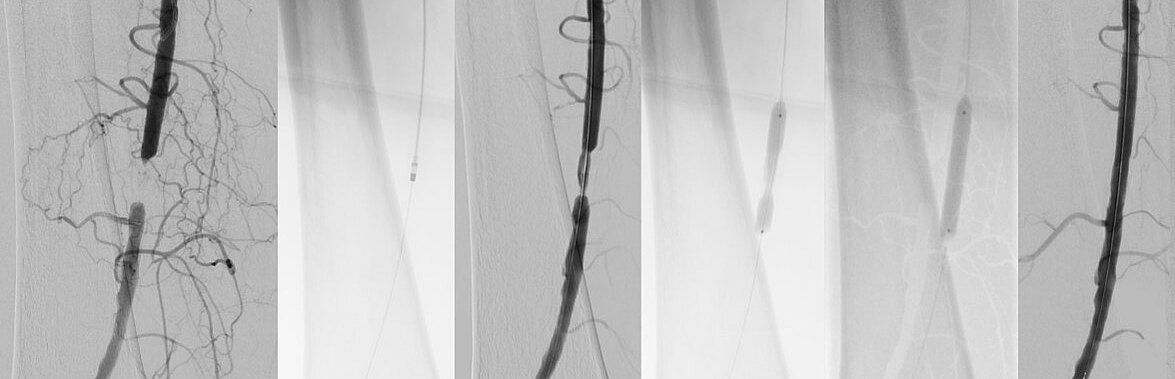

Gefäßeröffnende Therapie bei arteriellen und venösen Durchblutungsstörungen

Die Behandlung verengter oder verschlossener Blutgefäße - mit Ausnahme des Herzens - macht einen Großteil der bei uns durchgeführten Eingriffe aus. Dazu zählt die Therapie der peripheren arteriellen Verschlusskrankheit (Schaufenstererkrankung), Nierenarterienstenosen oder Engstellen der darmversorgenden Gefäße. Ein weiterer Teilbereich ist die Behandlung von Komplikationen bei Dialyseshunts.

Hierbei kommen verschiedenste hochmoderne Techniken zum Einsatz. Diese beinhalten die Aufdehnung von Engstellen mit einem Ballonkatheter oder die Stentimplantation (Angioplastie), das Absaugen von Thromben (Aspirationsthrombektomie), aber auch weitere hochspezifische Verfahren wie z.B. die Verwendung von „Gefäßfräßen“ (sog. Atherektomie) oder auch der Einsatz von Stoßwellen (Lithoplastie). Auch venöse Engstellen oder Gefäßverschlüsse können unter Einsatz endovaskulärer Techniken behandelt werden. Hierzu zählen zum Beispiel tumorbedingte Einengungen der großen Hohlvene oder auch Thrombosen.

Die Behandlung von Patientinnen und Patienten mit Gefäßerkrankungen erfolgt dabei in enger interdisziplinärer Absprache mit den Kollegen der Gefäßchirurgie, um die besten Behandlungsergebnisse zu erzielen.